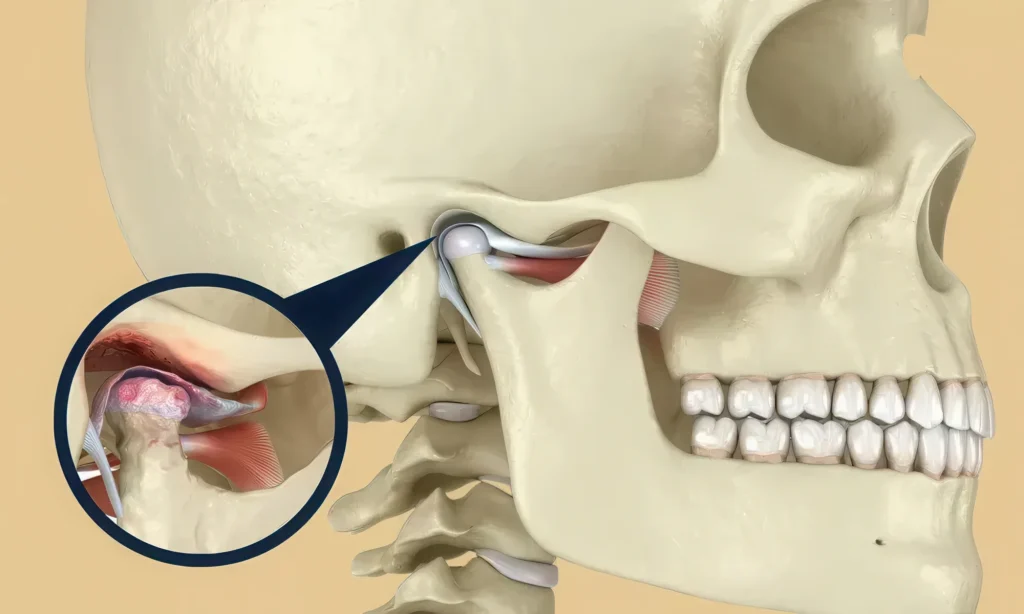

Когда говорю «заболевания ВНЧС», имею в виду весь спектр: дисфункции, ТМЖ-расстройства (TMJ расстройства височно-нижнечелюстного сустава), болевой синдром, нарушения работы сустава. Слова разные, суть одна: биомеханика системы «зубы — сустав — мышцы — осанка — дыхание» сбивается, и сустав начинает «жить» не по своим правилам.

Один отсутствующий моляр — и нагрузка перекраивается. Соседние зубы мигрируют, прикус уплощается, сустав ищет новую траекторию, а мышцы живут в режиме компенсации.

Травмы и перегрузки: где «щёлкнуло» — там и стартовало